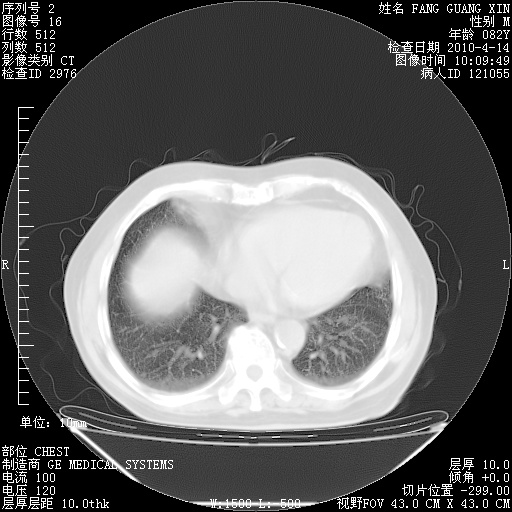

4月14日肺部CT

27.JPG

28.JPG

29.JPG

30.JPG